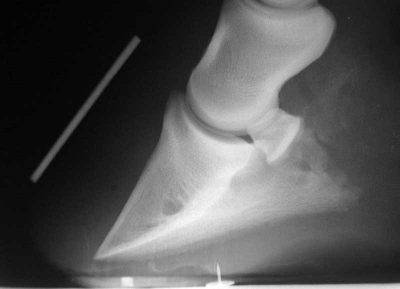

laminiteLa laminite indicata anche con i termini di rifondimento, rinfondimento, ripresa, riprensione, podoflemmatite pododermite asettica. E’ una malattia grave che coinvolge l’animale in toto anche se la sintomatologia clinica dominante riguarda il piede. E’ una patologia che nel 60% dei casi può portare alla morte del cavallo o ad un’invalidità permanente. Una condizione collegata alla laminite è il rinfondimento , il rimodellamento del piede dovuto alla rotazione verso il basso dell’osso triangolare all’interno del piede del cavallo. Oltre alla rotazione vi può essere una DISCESA della falange all’interno dello zoccolo.